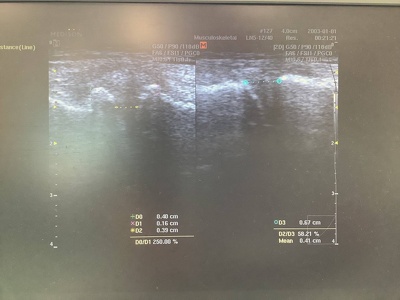

エコー画像

2022年08月04日(木)

エコーの画像によるケガや患部の状態の把握、確認ができます。